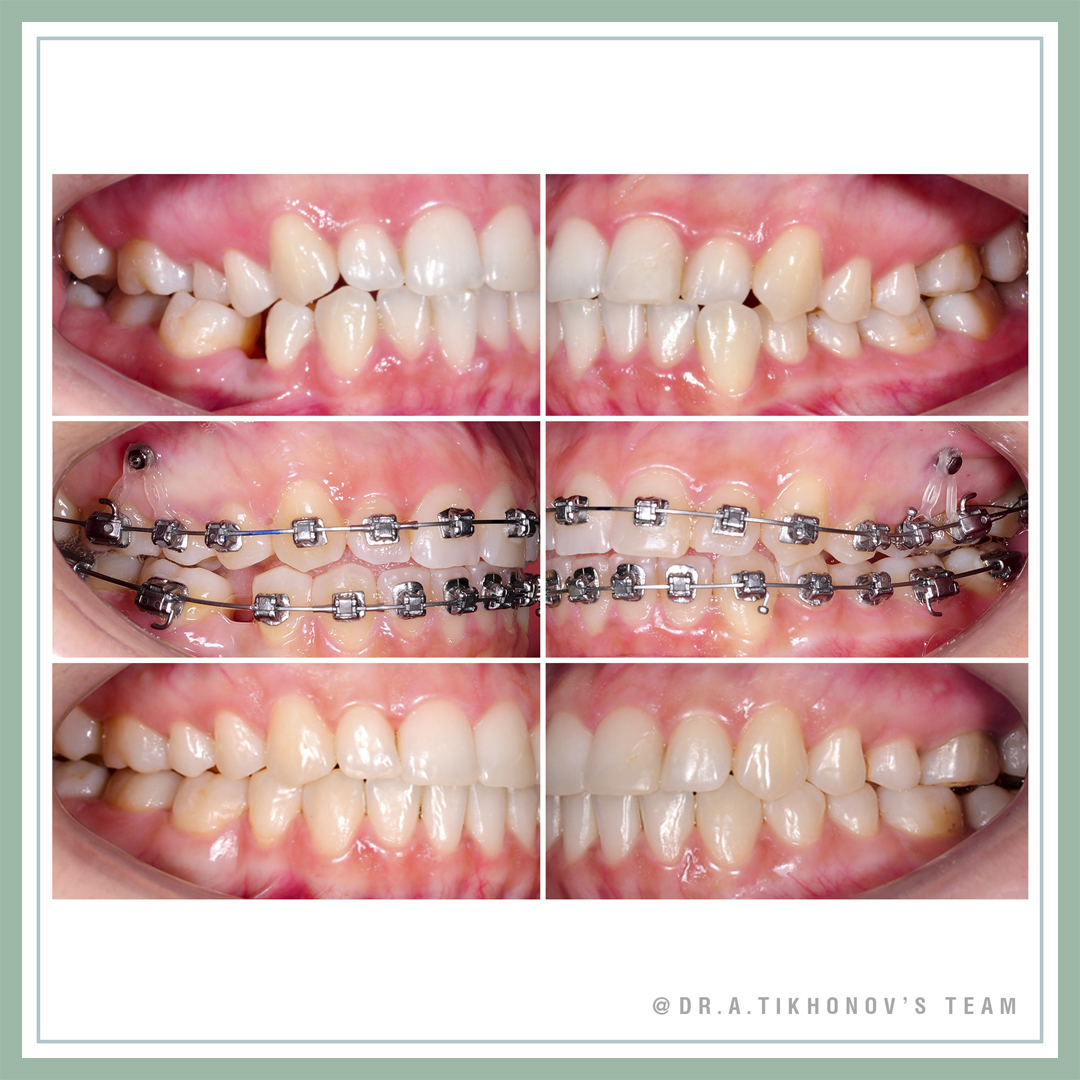

Коррекция арки улыбки и кривой Шпее интрузией с минивинтами

В современных реалиях, с наличием опыта и ортодонтических минивинтов, мы, конечно, решаем и параллельные задачи, старясь максимально улучшить эстетику улыбки наших пациентов. Минивинты применялись для внедрения 4, 5, 6 и выравнивания таким образом кривой Шпее.

Мы уже ранее обсуждали с вами в Блоге и регулярно разбираем на семинарах Школы ортодонтии и по минивинтам, что исправление Шпее в подобных случаях просто нивелированием без внедрения боковых, приведет к появлению десневой улыбки в переднем отделе, а также раскрытию прикуса из-за экструзии нижних боковых зубов. Внедрение боковых верхних зубов позволяет компенсировать этот побочный эффект, ну и конечно обеспечить естественную арку улыбки.

Smile arc and curve of Spee correction by posterior intrusion with TADs. Gummy smile in posterior segments corrected. 44 was extracted before our treatment by another doctor, so we closed this space achieving class III molar relationship. Do not forget, that you can do it only if lower 8 is in the arch.